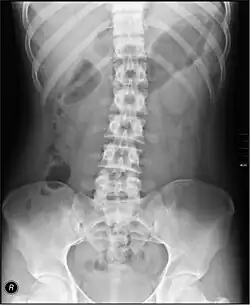

The standard abdominal X-ray protocol is usually a single anteroposterior projection in supine position.[15] A Kidneys, Ureters, and Bladder projection (KUB) is an anteroposterior abdominal projection that covers the levels of the urinary system, but does not necessarily include the diaphragm.

- Lumbar Spine - AP and Lateral +/- L5/S1 view in the UK, with obliques and Flexion and Extension requests being rare.[15] In the US, basic projections include an AP, two Obliques, a Lateral, and a Lateral L5-S1 spot to better visualize the L5-S1 interspace. Special projections are AP Right and Left bending, and Laterals with Flexion and Extension.

- Pelvis - AP only in the UK, with SIJ projections (prone) on special request.[15]